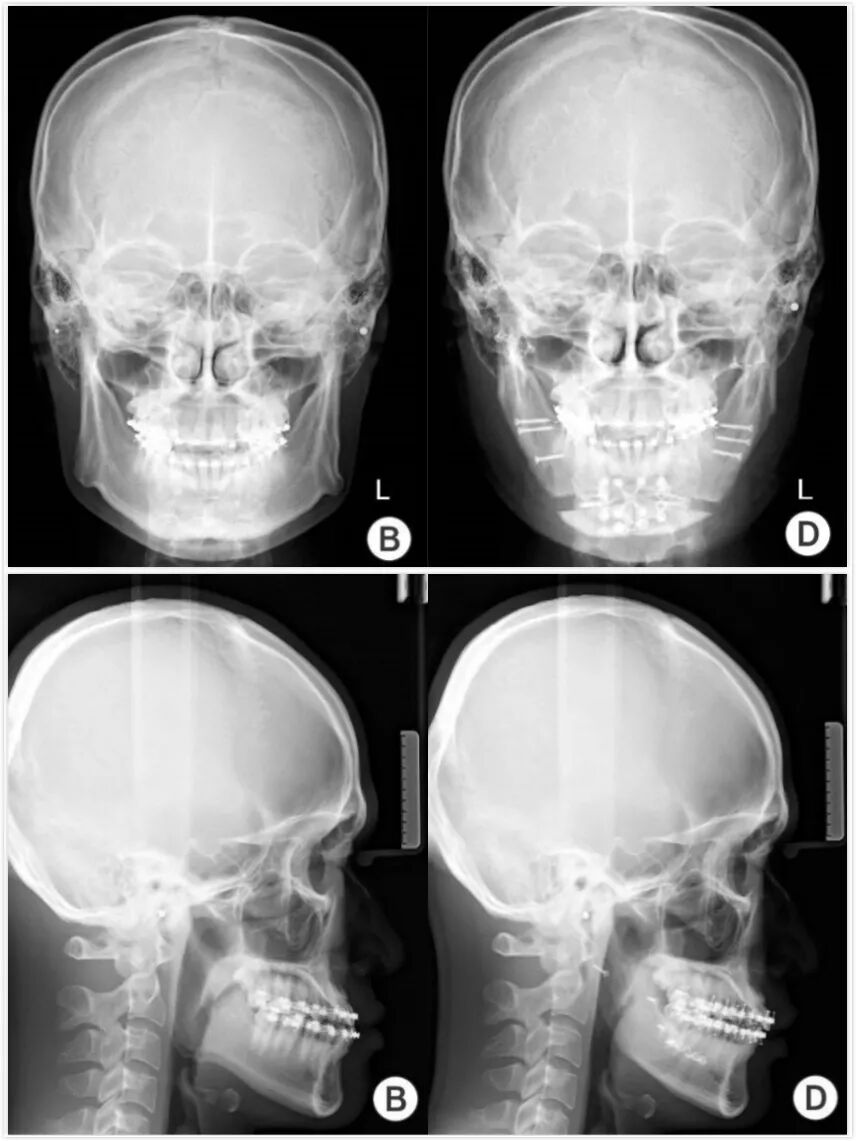

下颌角切除术的患者正侧面X片。左侧为术前X头影,可以看见明显外翻的下颌角。右侧为术后照片,从术后照片来看,他还做了颏延长手术| 文献[1]

下颌角截骨治疗之后会导致咬肌张力降低,患者在术后大约半年时间内会发生废用性萎缩,之后逐渐恢复。高加索人的咬肌肥大更加明显,可以在手术同时去除部分咬肌。而对于东亚人,如果确实有肌性肥大,截骨手术之后可以辅助注射少量A型肉毒素进行调整,达到更佳的效果。